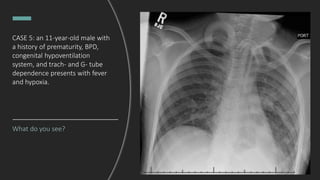

CASE 5: an 11-year-old male with

a history of prematurity, BPD,

congenital hypoventilation

system, and trach- and G- tube

dependence presents with fever

and hypoxia.

What do you see?

- Tracheostomy tube in the upper

third of the thoracic trachea.

- Scattered patchy

alveolar opacities throughout the

mid and lower left lung.